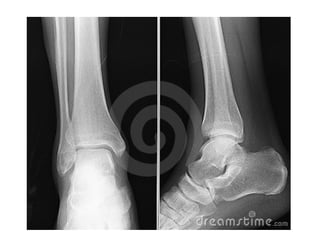

INCIDÊNCIAS PÉ

Flexão plantar Rotação externa